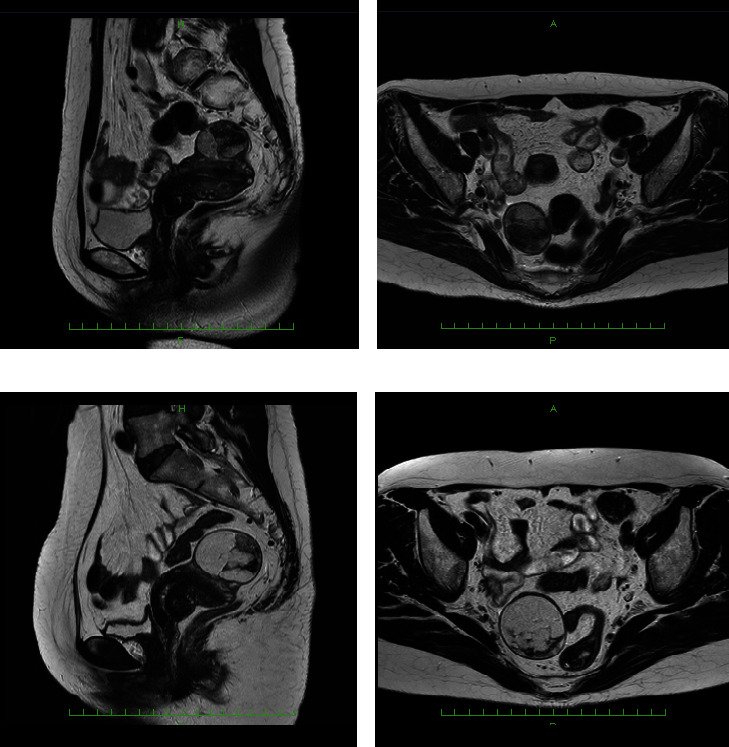

本研究报告了一例子宫脂肪肉瘤病例,并对相关文献进行了综述。患者 52 岁,经核磁共振检查确诊为脂肪组织肌瘤。患者的子宫体前壁有一个突出的肿块(39 × 32 × 41 mm3)。患者 58 岁时,她之前的医生发现肿瘤长大了,于是将她转诊到我院妇科。核磁共振成像显示,与之前的成像结果相比,肿瘤的大直径长了 1.23 倍,体积增大了 1.85 倍。弥散加权成像未发现明显异常信号。因此,恶性肿瘤被纳入鉴别诊断。患者同意接受全腹子宫切除术和双侧输卵管切除术。前壁的肿块完全留在子宫肌层中。腹腔内未发现种植,也未发现腹水。切口表面未发现出血或坏死。从组织病理学角度看,脂肪细胞和基质细胞的大小存在差异。细胞核结果不规则。免疫组化结果如下:CDK4(+)、desmin(+)、S100p(-)和 Ki - 67 = 1%。因此,诊断结果为分化良好的脂肪肉瘤。病灶位于子宫内,手术中将其完全切除。子宫原发的分化良好的脂肪肉瘤在完全切除后没有复发的可能,因此,患者接受了后续治疗,没有接受额外的治疗。术后 10 个月未发现转移或复发。

This study reports a case of uterine liposarcoma together with a literature review. At 52 years old, our patient was diagnosed with lipoleiomyoma by MRI. A mass (39 × 32 × 41 mm3) protruding from the anterior wall of the uterine body was observed. When the patient was 58, her previous doctor found that the tumor had grown, and she was referred to the gynecology department of our hospital. On MRI, the major diameter was 1.23-fold longer and the volume was 1.85-fold higher compared with the prior imaging findings. Diffusion-weighted images revealed no significant anomalous signals. Thus, malignant tumors were included in the differential diagnosis. The patient consented to total abdominal hysterectomy and bilateral salpingo-oophorectomy. The mass on the anterior wall remained completely in the myometrium. No implantation was found in the abdominal cavity, and ascites was not detected. No bleeding or necrosis was observed on the cut surface. Histopathologically, differences in the sizes of adipocytes and stromal cells were identified. There were irregularities in the nuclear findings. The immunohistochemical findings were as follows: CDK4 (+), desmin (+), S100p (-), and Ki - 67 = 1%. Therefore, a diagnosis of well-differentiated liposarcoma was rendered. The lesion was localized in the uterus, and it was completely removed during surgery. Well-differentiated liposarcoma of uterine primary has no possibility of recurrence following complete resection, and thus, the patient underwent follow-up without additional treatment. No metastasis or recurrence has been observed for 10 months after surgery.